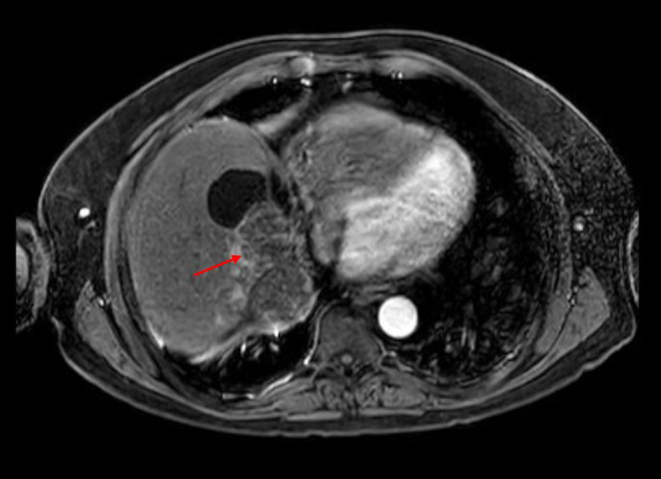

Selective internal radiation therapy (SIRT) is a novel intervention for both primary and metastatic malignant liver lesions. Adrenocortical carcinoma (ACC) is rare with limited treatment options; evidence for SIRT in ACC liver metastases consists of case reports only. Selective internal radiation therapy (SIRT) was employed to treat recurrent liver metastases in a 49-year-old gentleman with ACC, who previously underwent a left-sided hepatectomy. The patient opted for SIRT after reviewing the literature regarding mitotane chemotherapy and its toxicities. Selective internal radiation therapy (SIRT) provided several months of progression-free survival (PFS), with no toxicity and an excellent radiological response. The patient re-presented 12 years after the initial diagnosis with skeletal metastases and sadly died in September 2022. Substantial unmet need exists for effective treatments in ACC, with 75% of patients presenting with incurable disease. Developing widespread disease, SIRT offered 2 years' PFS in our patient; this was well tolerated with minimal residual liver impairment. Its use in ACC liver-limited disease warrants investigation.

Significance statement: Adrenocortical carcinoma (ACC) is a rare and aggressive tumour with limited treatments. Once metastatic disease develops, existing standard-of-care treatments offer a dismal overall survival, alongside marked toxicities. Selective internal radiation therapy (SIRT) may represent a new intervention in the treatment paradigm for liver-limited, metastatic ACC. Here, we present the case of a patient treated with multiple rounds of SIRT for relapsed, liver-limited ACC, prolonging survival by several years. Recurrent SIRT led to maintained liver function and no toxicities. Little evidence outlines its use in ACC but further study is certainly warranted to ascertain the value of SIRT, considering the limited treatment landscape that currently exists.